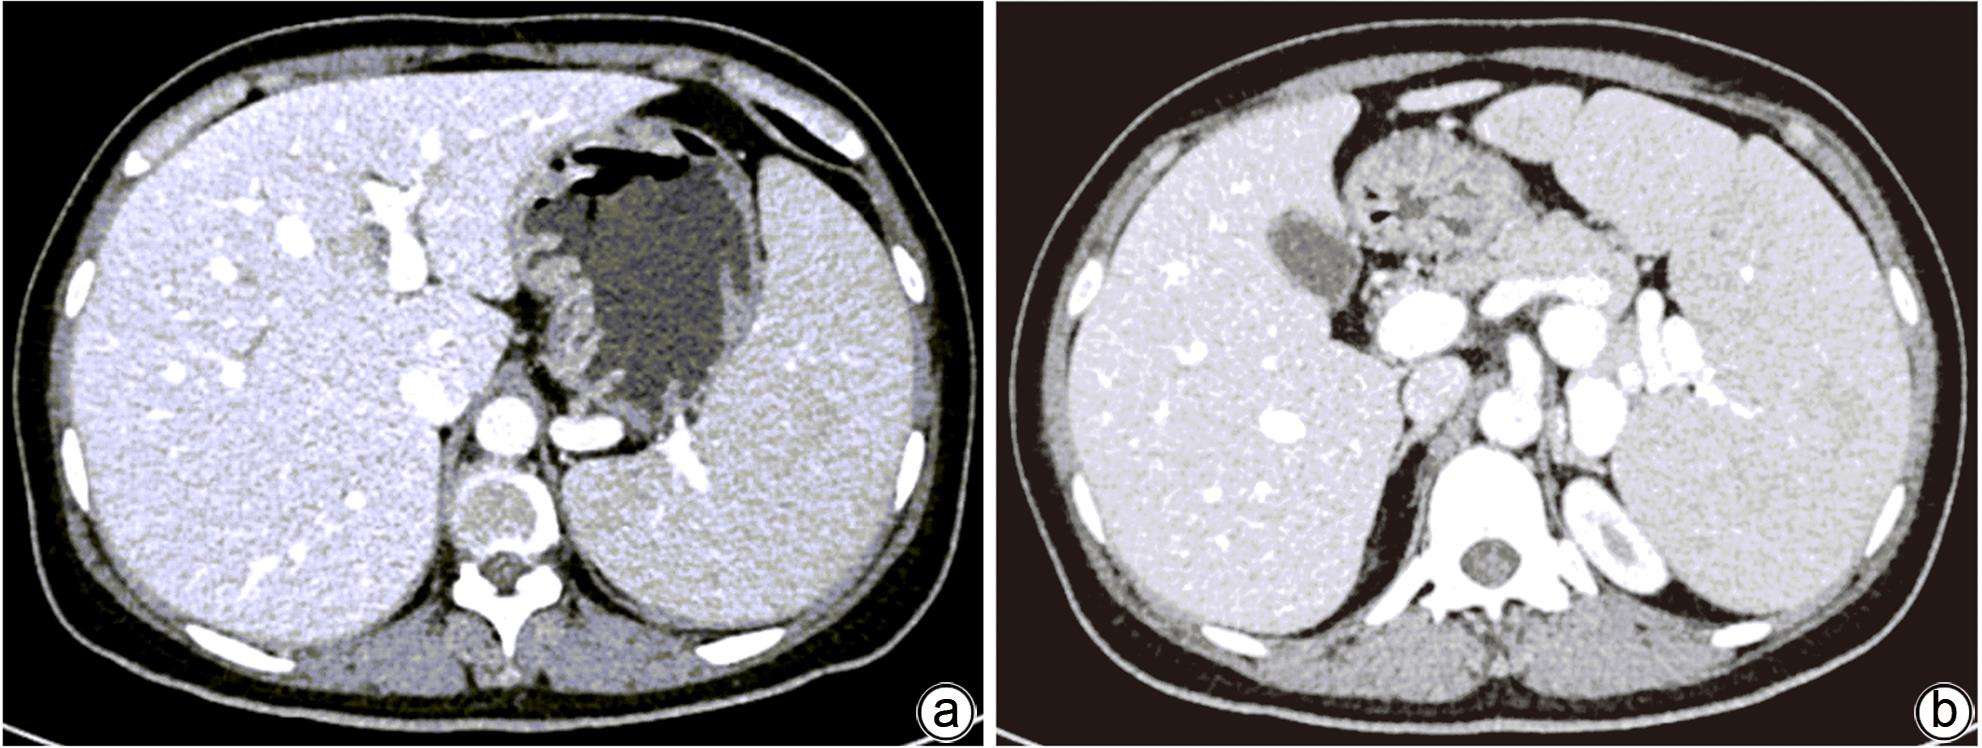

B型尼曼-皮克病及其肝脏受累的异质性表现1例报告

2024, 40(2): 356-360. DOI: 10.12449/JCH240221

摘要(1042) HTML (370) PDF (1123KB)(118)

摘要:

本文报道以“肝脾肿大待查”为主诉,经各项检查确诊为B型尼曼-皮克病的案例,并通过文献复习,总结B型尼曼-皮克病肝脏受累的异质性表现,旨在提高疑难罕见肝脏疾病的临床诊治水平。